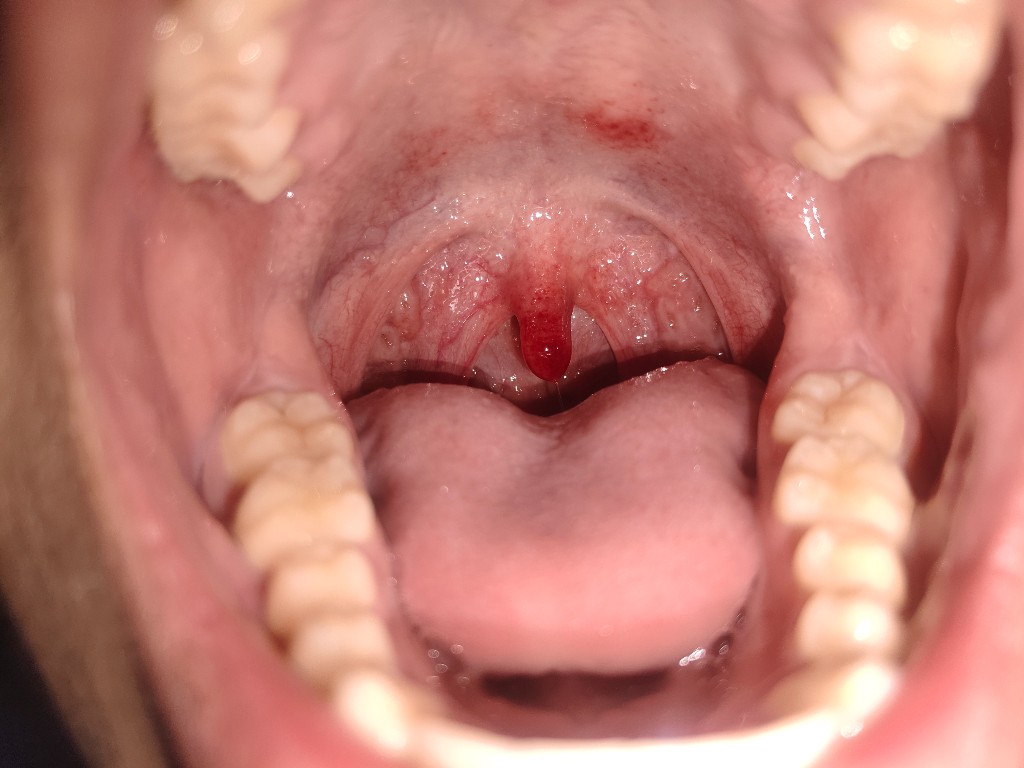

ผมควรทำยังไงครับอยากรู้เป็นอะไรรักษายังไง